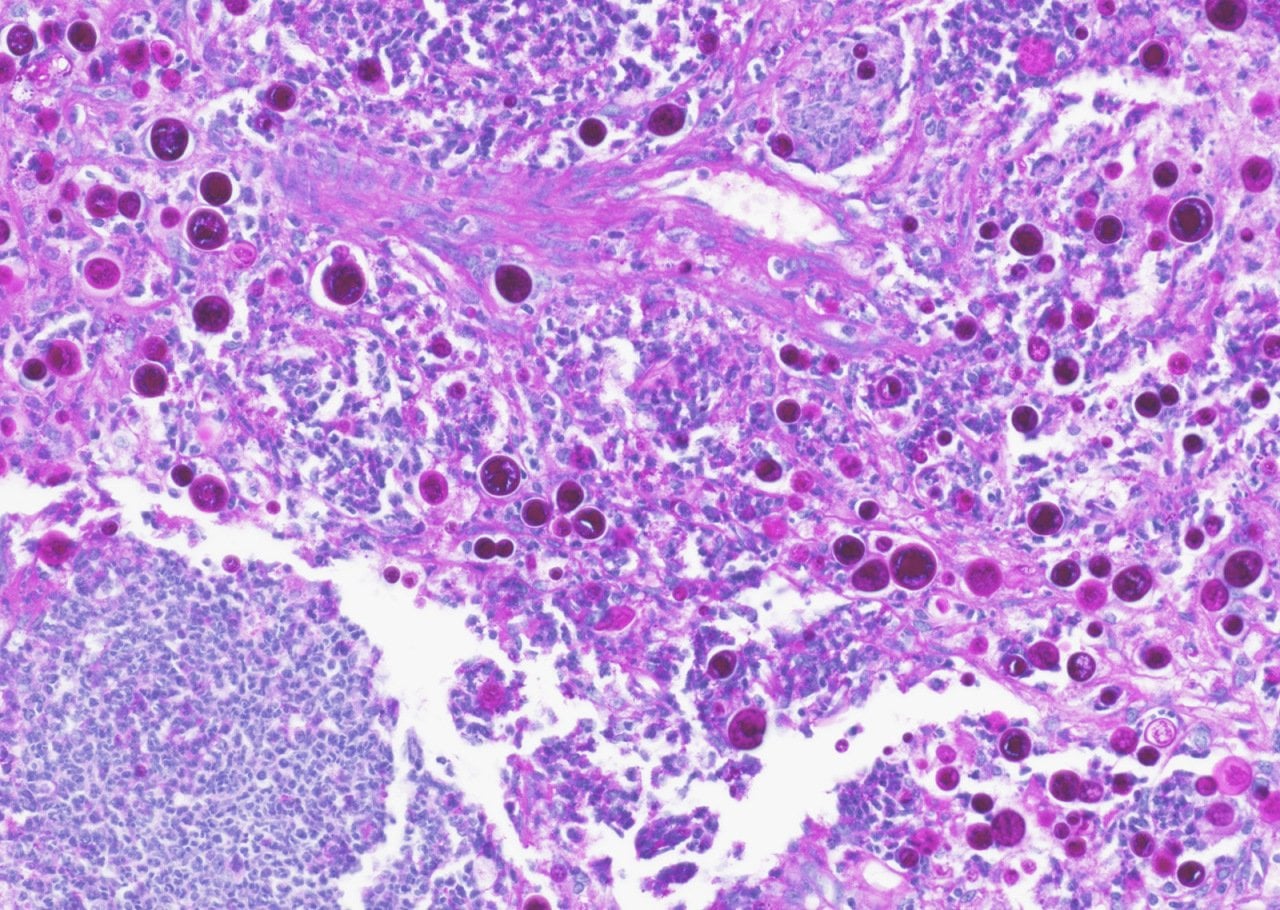

Most people who breathe in cocci spores — about six in 10 — won’t develop symptoms. But the 40% of exposed people whose immune systems can’t or won’t fight off the fungus develop symptoms such as fatigue, muscle aches, coughing, and rash that can last weeks or months. In the 5 -10% of symptomatic cases where the fungus invades the vital organs, the death rate is as high as 25%. The pathogen is so powerful that the U.S. army weighed whether to develop it into a bioterrorism weapon in the 1960s. (A histological slide of valley fever spores in the lung tissue of a dog is shown below.)